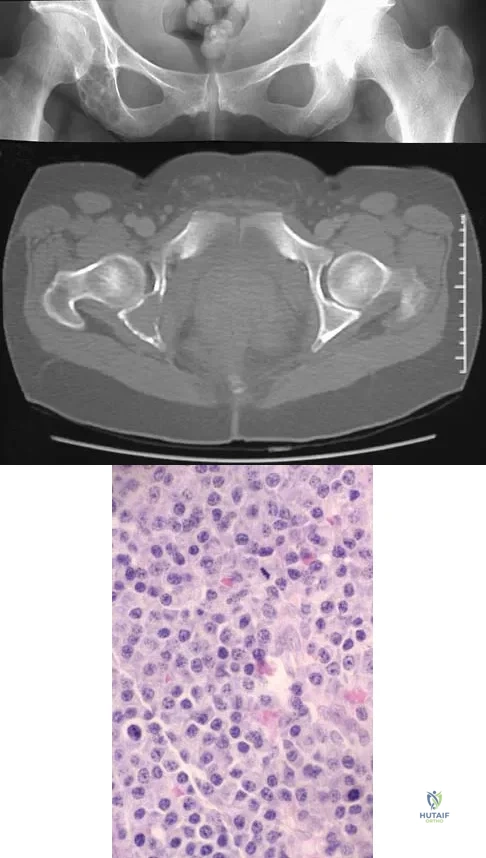

Question 18

A 47-year-old woman has had a 1-month history of left hip and medial thigh pain that is exacerbated by sitting. Laboratory studies show a total protein level of 8.2 g/dL (normal 6.0 to 8.0) and an immunoglobulin G (IGG) level of 2,130 mg/dL (normal 562 to 1,835). A radiograph, CT scan, and biopsy specimen are shown in Figures 38a through 38c. What is the most likely diagnosis?

Explanation